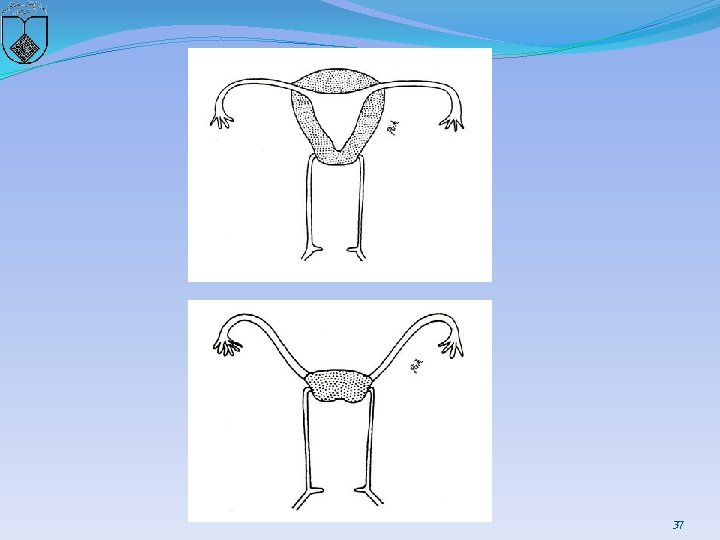

Two basic categories of cervical anomalies �first type: � cervical aplasia, lack a uterine cervix �lower uterine segment narrows: terminate in a peritoneal sleeve at a point well above the normal communication with the vaginal apex 30

31

�second type, cervical dysgenesis (1) Cervical body consisting of a fibrous band of variable �length and diameter (endocervical glands may be �noted on pathologic examination; (2) Intact cervical body with obstruction of the cervical �os (cervical ostium; the cervix is usually well formed, �but a portion of the endocervical lumen is obliterated; (3) Stricture of the midportion of the cervix (which is �hypoplastic with a bulbous tip and no identifiable �cervical lumen; (4) Fragmentation of the cervix (with portions that can �be palpated below the fundus and that are not connected �to the lower uterine segment 32

33